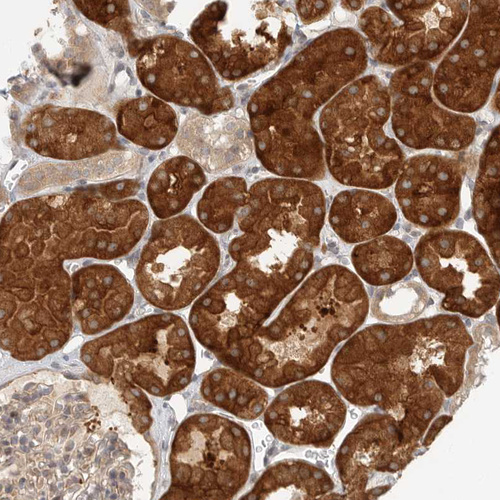

Immunohistochemical staining of human testis shows strong cytoplasmic positivity in cells in seminiferous ducts.